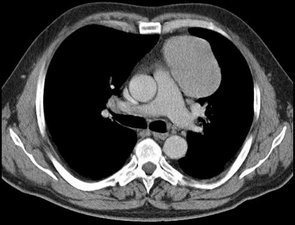

Operationen zur Abklärung unklarer Befunde

Unklare Rundherde in der Lunge erfordern in Abhängigkeit von ihrer Größe und vorliegenden Erkrankungen entweder eine engmaschige Kontrolle oder Abklärung. Eine sichere Diagnose ist allein vom Röntgenbild oder einer Computertomographie nicht möglich. Herde über 8mm Größe und solche, die nachweislich an Größe zunehmen, sollten unbedingt entfernt und untersucht werden.

Die Gewinnung einer Gewebeprobe kann auf verschiedenen Wegen erfolgen. Am sichersten ist die vollständige Entfernung des Herdes und histologische Untersuchung. Möglich sind auch eine Biospie mit einer Nadel von außen oder auch über eine Bronchoskopie (Lungenspiegelung).